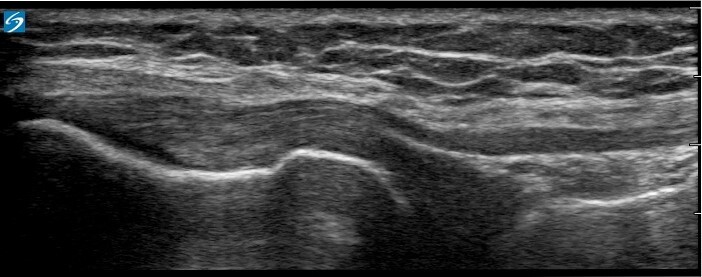

Knee Proximal Lateral Collateral Ligament (LCL) 2 Image